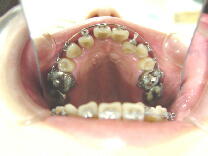

症例1 (10代 女性) 左右上下顎第一小臼歯抜歯例

初診時